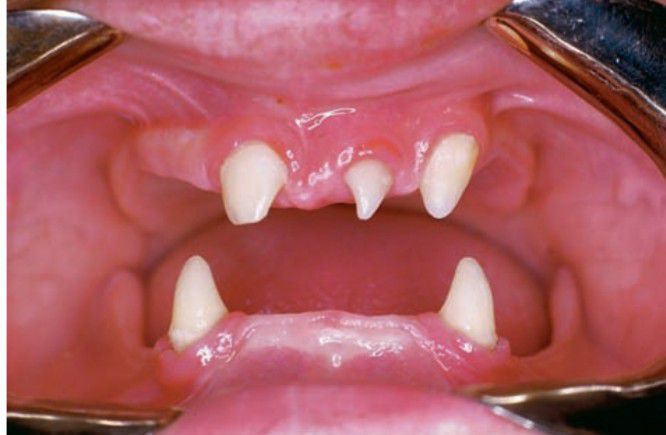

Ectodermal dysplasia

Hereditary ectodermal dysplasia with partial anodontia (hypodontia).